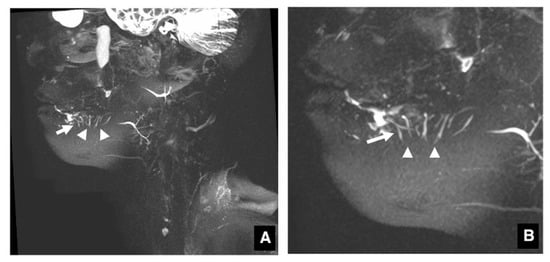

3.1. Visualization of Sublingual Gland Ducts by MR Sialography

3.2. Function of Sublingual Gland Ducts Evaluated by Dynamic MR Sialography

3.3. Clinical Application of MR Sialography for Patients with Sublingual Gland Diseases